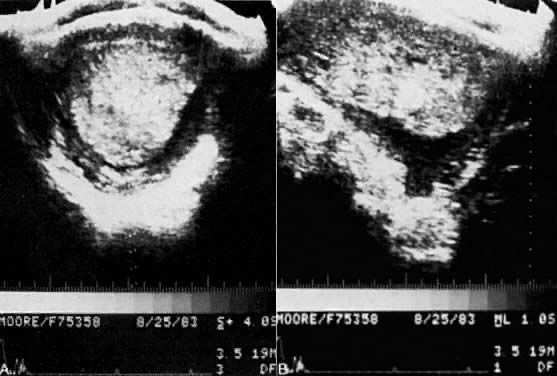

In contrast, complete hydatidiform moles have diffuse, often massive, hydropic degeneration of chorionic villi with diffuse trophoblastic proliferation that results in a differing spectrum of clinical signs and symptoms.24 Vaginal bleeding is the most common presenting symptom in patients with complete moles, often producing anemia.75 Up to half of all patients with complete hydatidiform mole will have uterine enlargement beyond the expected gestational age caused by expansion of the uterus by both molar tissue and intrauterine bleeding.75,76 Unilateral or bilateral ovarian enlargement produced by theca lutein cysts is clinically detected in one fourth to one third of patients with complete hydatidiform mole and is usually associated with hCG levels above 100,000 mIU/ml (Fig. 12).75,76,77,78 Preeclampsia and hyperemesis each occur in approximately one fourth of patients with complete mole. The majority of patients with these symptoms also usually have markedly elevated hCG values.75 The development of pregnancy-induced hypertension before 24 weeks' gestation is almost diagnostic of molar pregnancy. Increases in thyroid hormones are frequently diagnosed in patients with complete hydatidiform moles, but clinical hyperthyroidism is detected in less than 10%.79 There is no consistent relationship between serum hCG values and results of thyroid function tests. Finally, in contrast to partial moles, patients with complete moles have approximately a 20% incidence of trophoblastic tumor after evacuation, with 10% to 20% of these having metastatic disease.76,77,80,81,82,83,84,85,86,87 The majority of those with trophoblastic tumors have invasive or persistent mole while approximately one fourth to one third have gestational choriocarcinoma.

The diagnosis of hydatidiform mole is no problem after the patient passes molar vesicles. Even then, however, ultrasound should be used to exclude the presence of a fetus (as in partial mole or twin gestation), as well as to further define the presence and size of theca lutein cysts of the ovaries (Fig. 13). A variety of other physical and chemical tests have been used over the years, including amniography, arteriography, computed tomography (CT), and magnetic resonance imaging (MRI), but few are indicated beyond standard pelvic ultrasound. Tests for hCG may occasionally be useful in the differentiation of hydatidiform mole from normal pregnancy. Serum assays may be used, and the results should be compared with the hCG levels of normal pregnancy at the gestational age in question. Although a single result well above normal range for that state of pregnancy suggests molar pregnancy, only the results of serial assays are definitive. Delfs80 has asserted that between days 60 and 100 of pregnancy there is no level of hCG secretions, however high, that could not be caused by a normal pregnancy or some variation thereof. Thus, gonadotropin levels in excess of 100,000 IU to 200,000 IU/24-hr urine collection or their equivalent serum levels are compatible with molar pregnancy, with the exception of the peak elevations seen between weeks 9 and 14 of normal pregnancy. Higher levels may also be associated with multiple gestation or toxemia of pregnancy. A continued rise in hCG levels after the 14th week of pregnancy (the hCG level drops at this time in normal pregnancy) is the best evidence of a molar pregnancy that can be obtained by hCG assay (Fig. 14).

Fig. 13. Pelvic ultrasound of hydatidiform mole in situ. A. Transverse view of the uterus showing mole in situ. B. Longitudinal section of the molar pregnancy.(Courtesy of Dr. James Bowie)

Fig. 14. Mean value and 95% confidence limits describing normal postmolar β-hCG regression curve.(Schlaerth JB, Morrow CP, Kletzky OA et al: Obstet Gynecol 58:478, 1981. Reprinted with permission from The American College of Obstetricians and Gynecologists.)